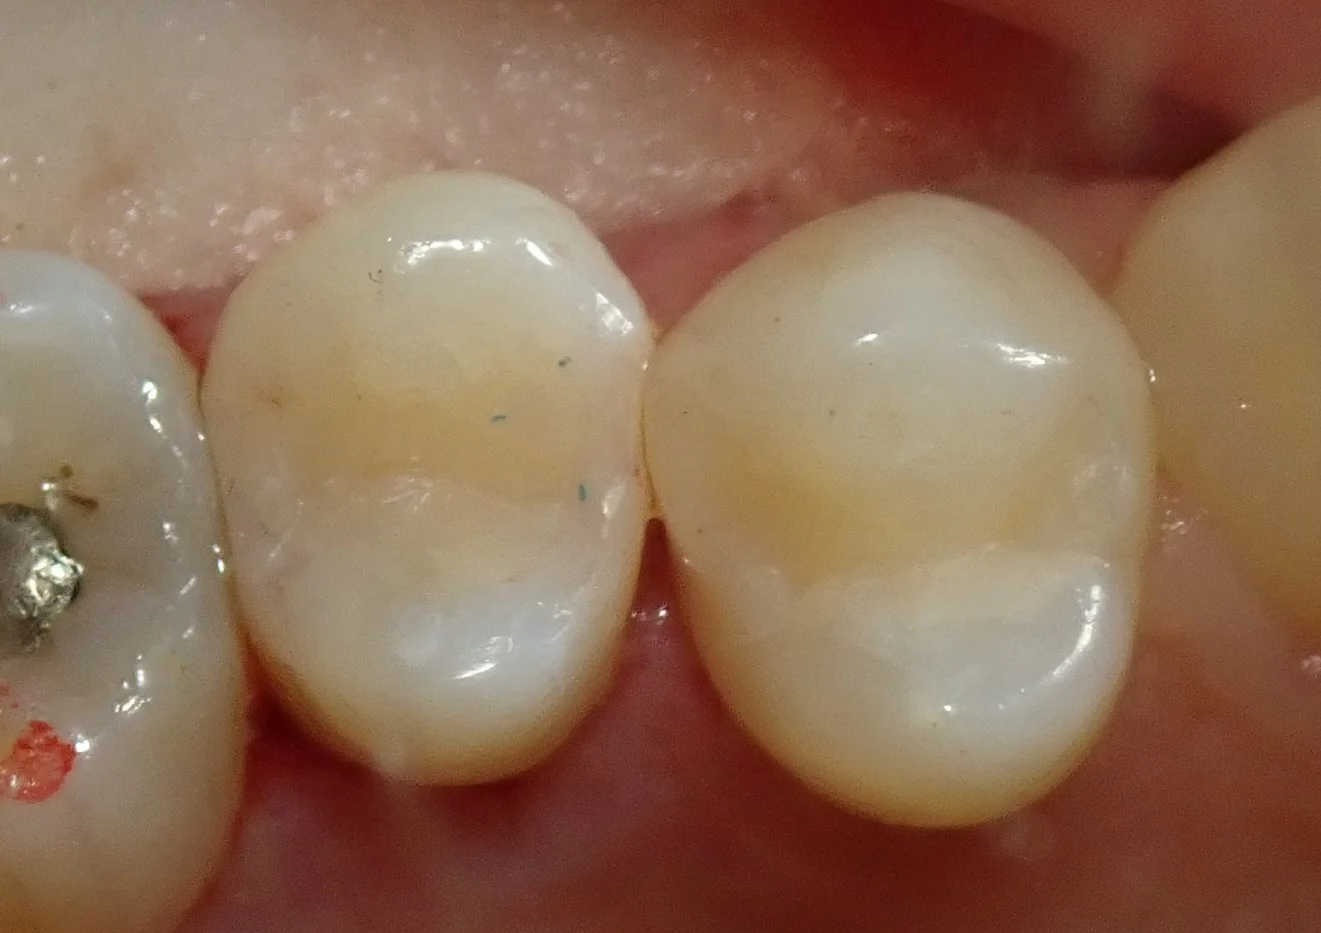

そして、詰め終わったのがこちらです。

前後的に歯がズレていたので、なるべく本来あるべき形に治しました。

ここまでやるのは保険上だとちょっと審美領域に掛かってくるので、微妙なところなんですが・・・

それでも本来あるべき形に戻したいという欲求が出ちゃうので、ついついやっちゃいますね(笑)